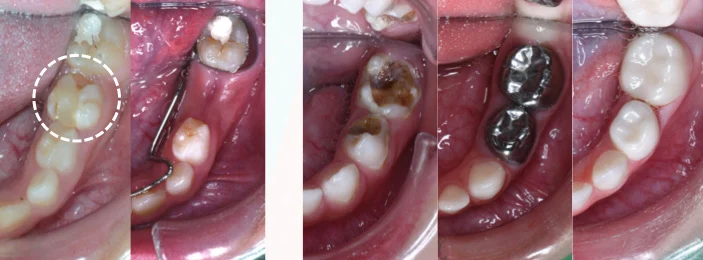

蛀牙範圍過大或是做過根管治療的乳牙,必須以牙套保護起來,以防止崩裂或是再次蛀牙,導致牙齒再受到傷害!乳牙牙套會隨著乳牙一起脫落,並不會影響換牙!